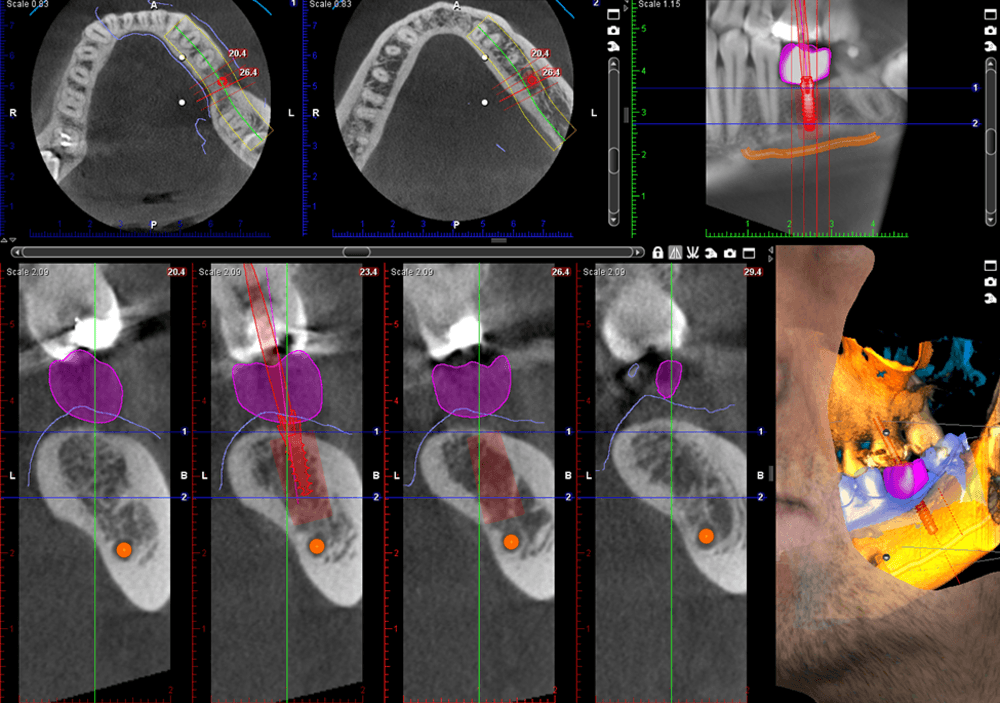

Meet the Planmeca ProMax® 3D imaging family, a comprehensive suite of solutions tailored to meet the unique demands of dental practices. With unparalleled image quality and cutting-edge technology, these systems provide practitioners with the versatility and precision needed for accurate diagnostics and treatment planning.

Discover the Planmeca ProMax® 3D family, meticulously designed to meet the needs of every dental practice. Known for its unparalleled image quality, each system reflects Planmeca's commitment to excellence. Equipped with noise reduction technology, these units deliver unmatched image clarity. Enjoy True Extraoral bitewings, segmented pans, and AutoFocus for crystal clear pan images every time. Available features like Planmeca Ultra Low Dose™ and Planmeca CALM® for patient safety